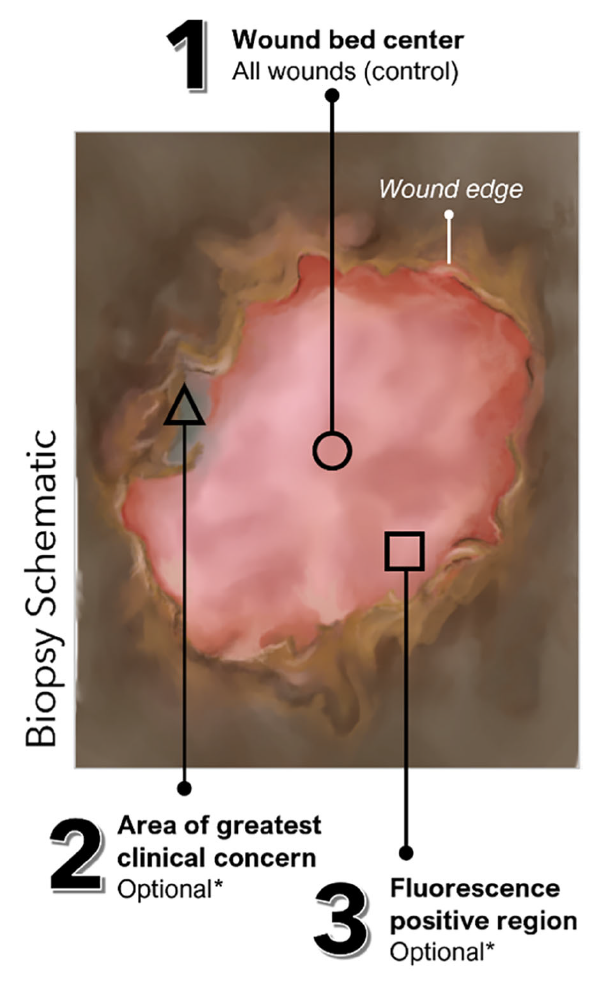

Use of fluorescence imaging (FL) to optimize location of tissue sampling in hard-to-heal wounds

Serena, TE et al. Front Cell Infect Microbiol 2022